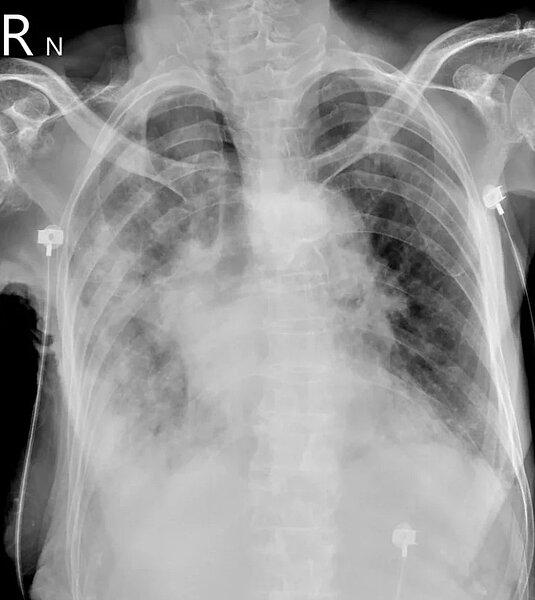

蘇一峰在臉書PO出一張患者「大白肺」X光片,他表示,比起來大肆宣傳的黴漿菌肺炎根本不可怕,重症大白肺還是以COVID為主,至於肺部X光片的患者努力好幾天,「目前看起來是救回來了」。